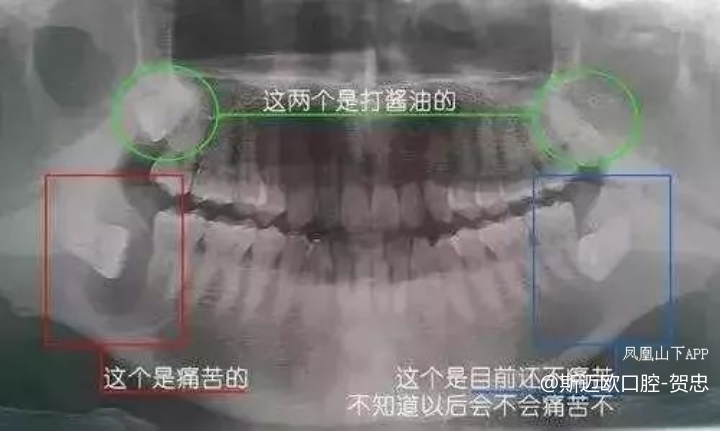

①牙齿本身:生长方向,牙根数目,牙根是否弯曲、膨大等。

②与重要的解剖结构的位置关系:如上颌磨牙与上颌窦的关系;下颌磨牙与下颌神经管的关系;儿童在混合牙列期恒牙与乳牙胚的关系等。可以减少拔牙的风险。

③预知其他病变:如颌骨内有无埋伏牙,多生牙,囊肿等。

先放几张图,让你们涨涨姿势,不拍片根本不知道你的牙齿长得会有多奇葩!